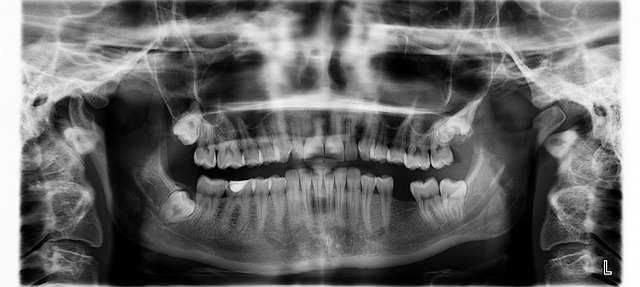

Um mehr über den fehlenden Zahn – oder manchmal auch mehrere – zu erfahren, erstellt der Zahnarzt zuerst eine Röntgenaufnahme, auf der mögliche Nichtanlagen zu sehen sind. Danach können weitere Diagnosen festgestellt werden. Zum Beispiel die Enge des Zahnlückenraums oder bereits begonnene Verschiebungen der benachbarten Zähne.

Hypodontie lässt sich am Röntgenbild erkennen.